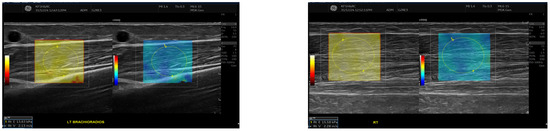

Exploratory Assessment of Muscle Thickness and Stiffness Around Arteriovenous Fistulas Using Shear Wave Elastography

Background/Objectives: Muscle thickness and stiffness near the arteriovenous fistula (AVF) site may influence vascular access function in hemodialysis patients. This exploratory study aimed primarily to describe differences in muscle thickness and stiffness between the AVF-bearing and contralateral limbs, and secondarily to examine [...] Read more.

Background/Objectives: Muscle thickness and stiffness near the arteriovenous fistula (AVF) site may influence vascular access function in hemodialysis patients. This exploratory study aimed primarily to describe differences in muscle thickness and stiffness between the AVF-bearing and contralateral limbs, and secondarily to examine whether these parameters were associated with AVF maturation. This study aimed to compare these muscle parameters between the AVF and contralateral sides and to evaluate their relationship with AVF maturation status. Methods: Thirty participants undergoing hemodialysis were included, comprising 22 with mature AVFs and 8 with non-mature AVFs. Ultrasound examinations measured muscle thickness and stiffness using Shear Wave Elastography (SWE) of the biceps brachii and brachioradialis muscles. Volume flow was recorded in the draining vein and feeding artery. Statistical analyses included paired comparisons, group comparisons, Pearson correlations, and multiple linear regression models. Results: Brachioradialis thickness was significantly reduced on the AVF side compared with the contralateral side (p = 0.013, Cohen’s d = –0.95), particularly in forearm (radiocephalic) fistulas (Wilcoxon p = 0.014, Cohen’s d = –0.95), indicating localized muscle atrophy. No significant side-to-side differences were found for biceps brachii thickness or for stiffness in either muscle (all p > 0.1). Comparisons between mature and non-mature AVF groups showed no significant differences in muscle parameters on the AVF side (all p > 0.4). Conclusions: AVF may lead to asymmetric muscle changes, especially a reduction in brachioradialis thickness, regardless of maturation status, which could affect forearm function. Nevertheless, muscle thickness and stiffness do not appear to predict AVF maturity or vascular access success directly. Full article

Show Figures

Figure 1